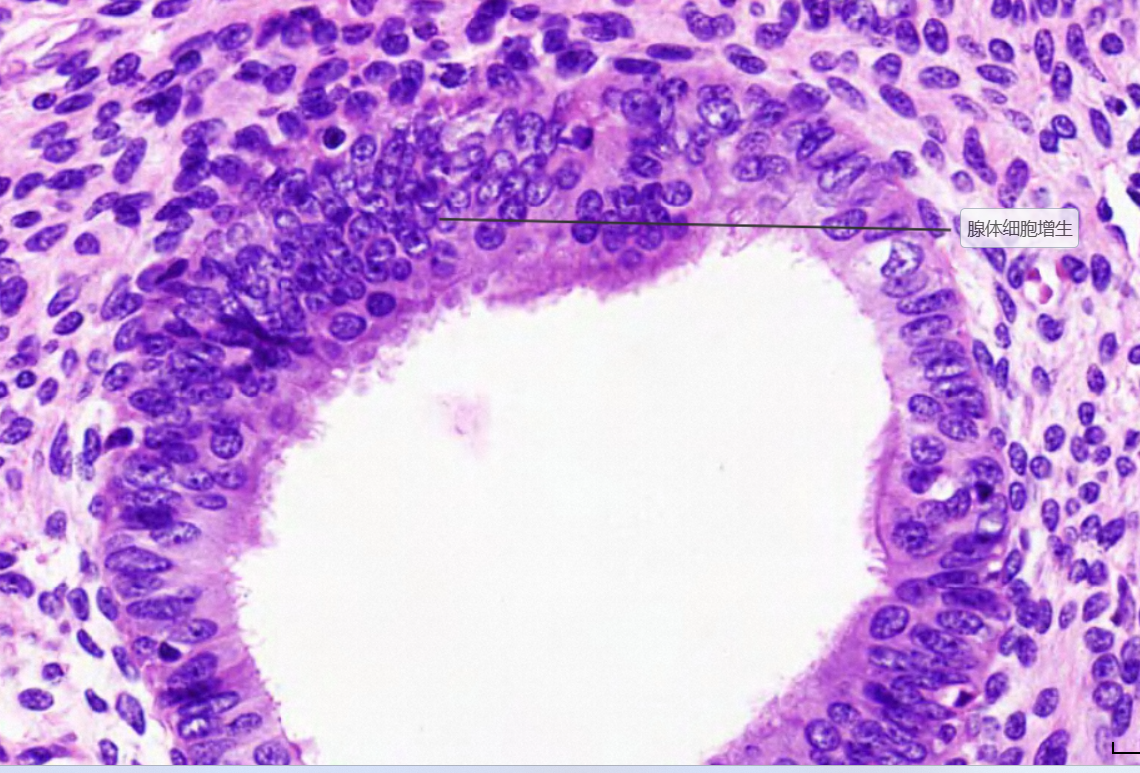

4 卵巢黏液腺癌

3.癌细胞